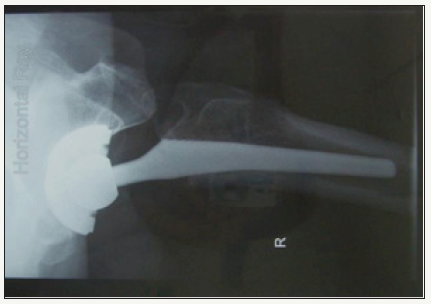

At six week follow-up he did report one episode of instability a week prior when getting up from a chair and he felt a sudden “pop” in his hip with flexion but otherwise continued to mobilise independently. At 14 months post-op he presented acutely after bending forwards, again flexing at his hip, and feeling something “pop” in this hip. He was unable to mobilise. On further questioning he reported multiple episodes of instability during the past year. X-Rays showed an eccentrically placed femoral head with no evidence of femoral or acetabular loosening or shift (Figure 3 & 4).

figure 4: Liner disassociation on lateral (horizontal ray) film.